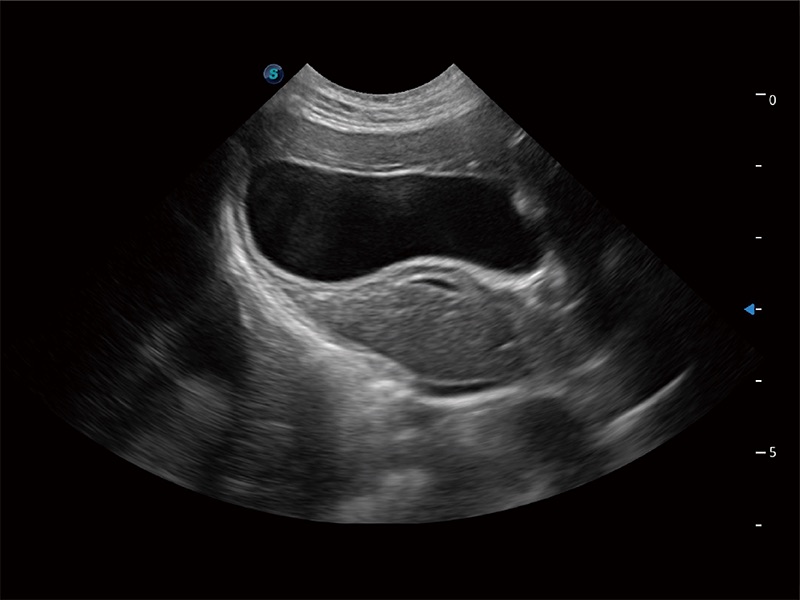

优异的基础图像

ProPet 80 全新的动物超声智能软件和丰富的探头群,为动物医生提供了高清晰度和精细分辨率的图像,无论在宠物、马科、畜牧还是实验室动物等应用中都可以轻松应对,为您的日常工作带来满意的体验。

(猫)胆囊

(犬)胎儿四腔心